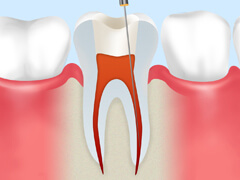

根管治療とは、歯の中にある「根管」という細い管の中から、虫歯菌に冒されて死んでしまった神経や血管を取り除き、内部をきれいに洗浄・消毒して薬剤を充填する治療です。根管はとても細かく複雑に枝分かれしているため、この治療は簡単ではありません。しかし、確実に行えれば歯を残すことができるのです。

| 虫歯菌に冒されて死んでしまった神経・血管を除去します。 | 根管の長さを正確に測ります。 | 根管内に汚れが残らないよう、歯の内部をきれいに洗浄します。 | 薬剤を使って、内部を殺菌・消毒します。 | すき間ができないよう、薬剤をすみずみまで充填します。 | 土台を入れ、上部に被せ物を装着して治療完了です。 |

ニッケルチタンファイルを使用しています

当院では根管内の神経・血管を除去する際に、柔軟な弾性を持つニッケルチタンファイルを使用しています。複雑に湾曲した根管にもしっかりフィットするため、根管内を傷つけないうえ、すみずみまでの汚れをきれいに取り除くことが可能です。 |